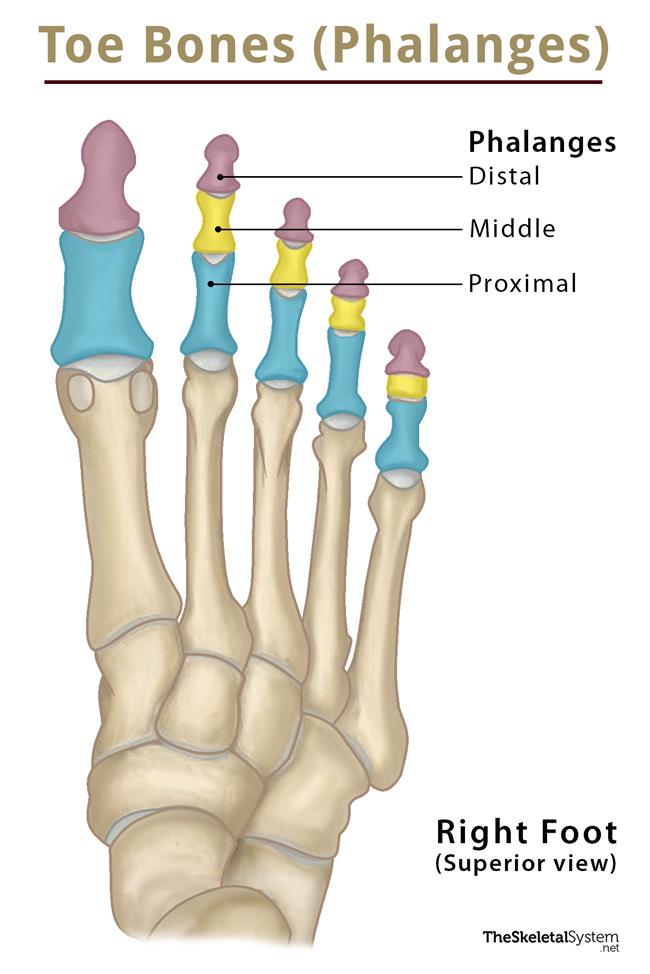

how are the phalanges of the foot based on?

distal

middle

proximal

what are the landmarks of the phalanges of the foot?

base

shaft

head

what do the phalanges of the foot look like?